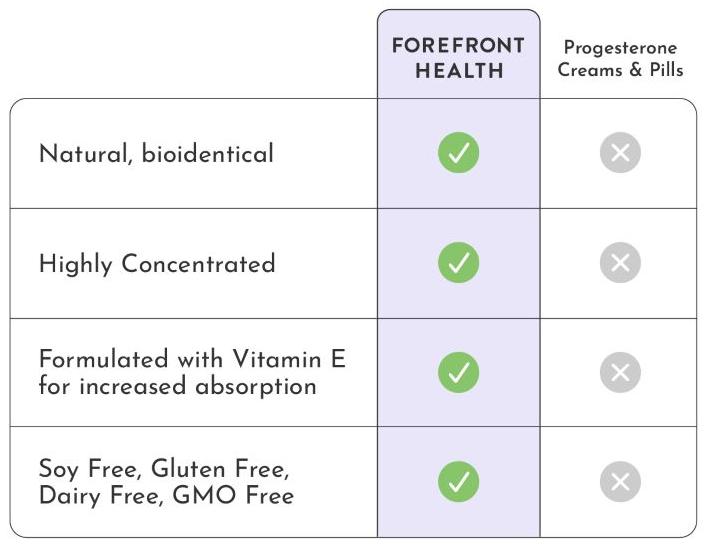

Our bio-identical progesterone is designed and formulated like no other. Unlike progesterone creams that are typically low concentration or contain thyroid suppressive oils, or progesterone pills / tablets that are largely inactivated by your liver, or suppositories that are prone to crystallization and can’t be absorbed… Progesterone Oil solves all of these problems. It’s highly concentrated at more than 10% progesterone, doesn’t crystalize, and contains a special solution allowing for close to 100% absorption. The secret lies in the special formulation with Vitamin E, which acts as a carrier to deliver the progesterone directly into the bloodstream. This makes it the quickest and most absorbable bio-identical progesterone source available.